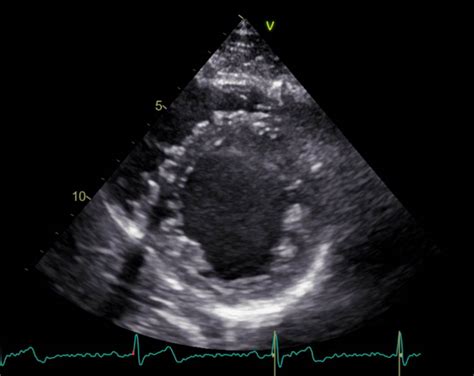

Predležeča posteljica, medicinsko znana kot placenta previa, je stanje, pri katerem se posteljica nahaja nizko v maternici, deloma ali v celoti prekriva notranje maternično ustje (NMU). To lahko predstavlja resno tveganje, saj lahko med nosečnostjo ali med porodom povzroči obsežno krvavitev. V primeru, da je posteljica popolnoma prekrivala NMU (placenta previa totalis), je tveganje za zaplete še toliko večje. Zapleti se lahko pojavijo tudi, če posteljica sega preko NMU s stanjšanim delom, kar je bilo ugotovljeno v enem od opisanih primerov.

Zaskrbljenost glede predležeče posteljice je še toliko večja, če je nosečnost že tvegana, na primer po predhodnem carskem rezu (CR). V takšnih primerih je maternična stena lahko že oslabljena, kar povečuje možnost zapletov, kot je vraščanje posteljice (placenta accreta, increta ali perkreta). Placenta accreta pomeni, da se posteljica vrašča v mišični sloj maternice, placenta increta pa še globlje, v samo steno maternice, medtem ko placenta perkreta pomeni, da posteljica preraste celotno steno maternice in se lahko širi v sosednje organe, kot je sečni mehur. V takšnih ekstremnih primerih je lahko nujna odstranitev maternice (histerektomija), da se reši življenje nosečnice.

V primerih, kot je placenta previa, še posebej če obstaja sum na vraščanje posteljice (placenta accreta), so lahko potrebni dodatni pregledi. Cistoskopija je ena izmed teh preiskav, ki lahko pokaže, ali posteljica vrašča v sečni mehur. To je pomembna informacija, saj vpliva na načrtovanje poroda in morebitne kirurške posege.